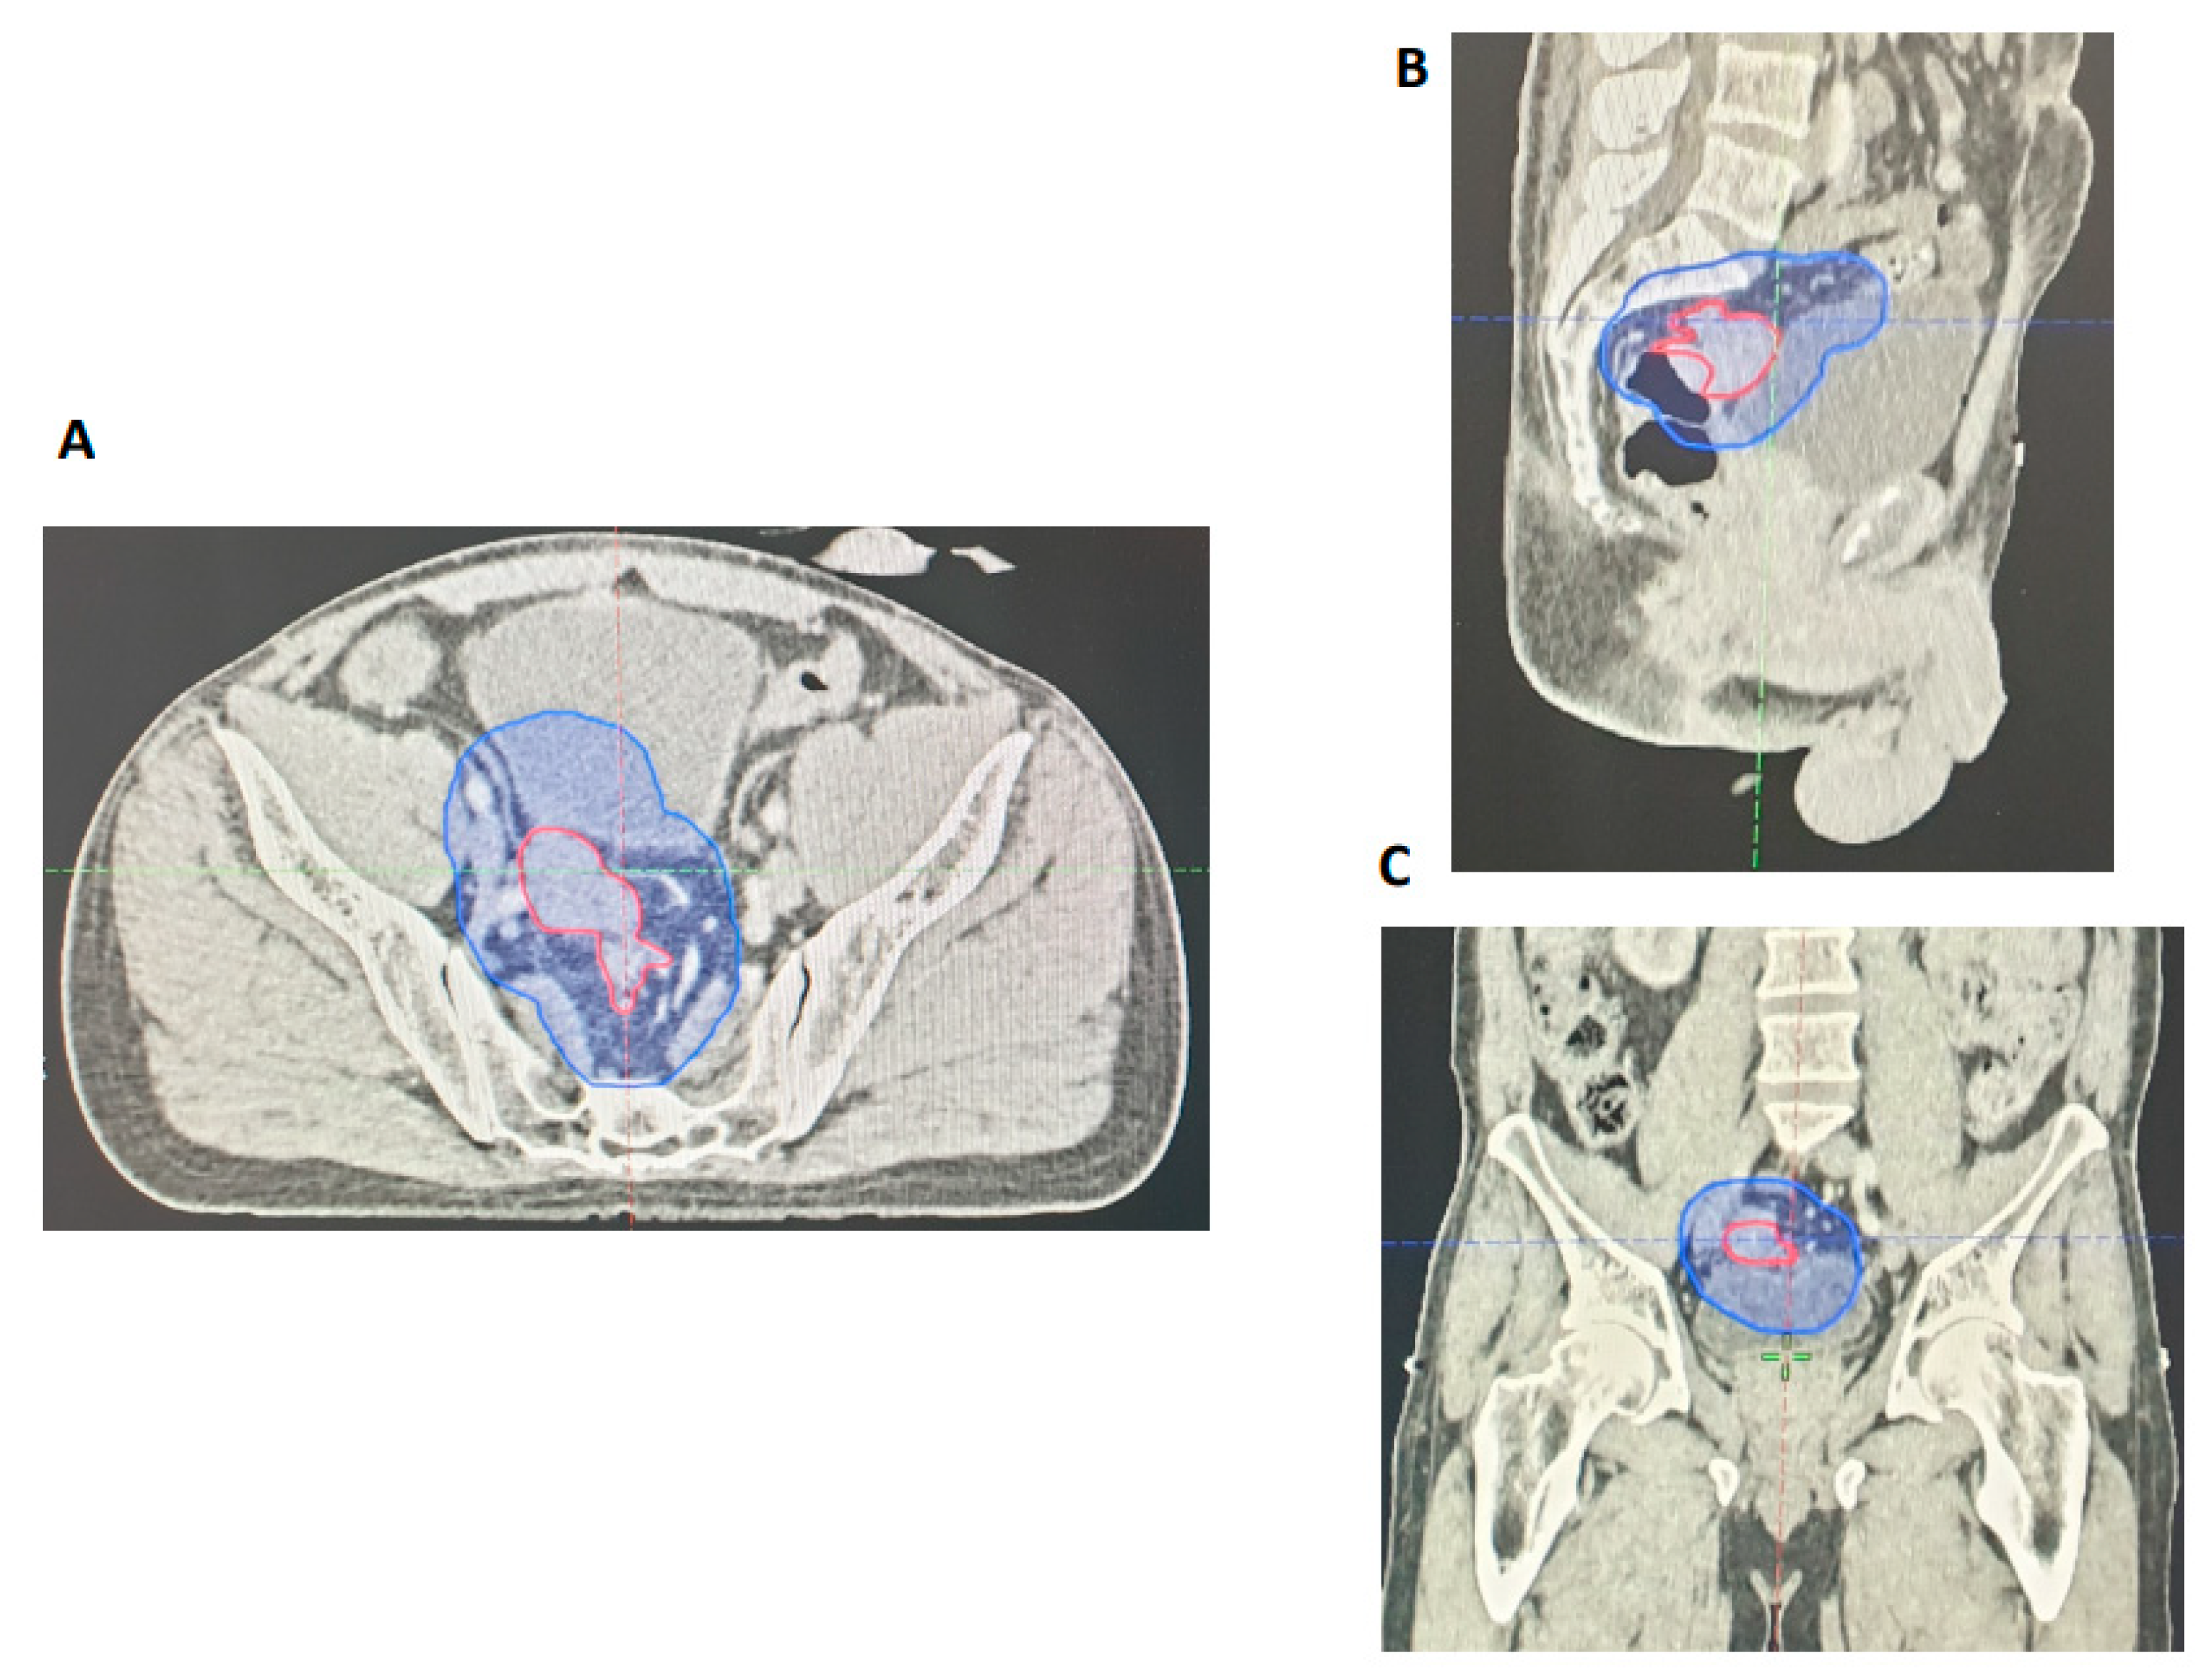

3.2.2. Retrospective Assessment of GTV Delineation by GI Radiologists

The GTVs were retrospectively evaluated by two independent GI radiologists for all 27 patients included in the re-evaluation phase. Areas of GTV geographical miss were recorded. Similar to our initial study, our results revealed that all primary tumours were adequately encompassed within the GTVp. Nodal assessment showed that there was geographical miss for two patients (7%) within the GTVn, but all involved nodes were encompassed by the PTV45Gy. We also reviewed the accuracy of EMVI delineation for each of the 27 cases. Bearing in mind that most of these cases were EMVI positive (89%), an independent radiology review showed that there was partial GTV geographical miss in only one patient (4%) (Figure 4). All things considered, this formal re-evaluation of our practice following adjusted MRI reporting and detailed discussion in MDT has shown a notable improvement in GTV delineation with respect to involved nodes and areas of EMVI.

Figure 4.

Radiotherapy planning CT showing contiguous EMVI extending from the primary tumour (red) encompassed within the PTV (blue). (A) Axial view. (B) Sagittal view. (C) Coronal view.